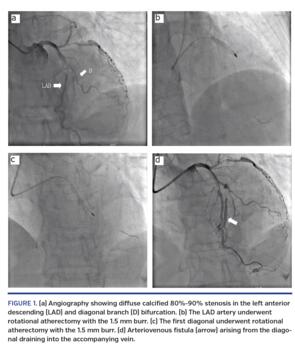

A 67-year-old man with a history of hypertension and gastritis presented to our institution with unstable angina. Coronary angiography demonstrated diffuse calcified 80%-90% stenosis in the LAD and diagonal branch bifurcation (Figure A; Video 1). The patient was referred for RA. In order to avoid occlusion of the side branch, RA was also planned in the diagonal branch. RA was performed in the LAD with a 1.5 mm burr (Boston Scientific) at 160,000 rpm for a total of 40 seconds (Figure B; Video B) and in the first diagonal using the same 1.5 mm burr at 160,000 rpm for a total of 30 seconds (Figure C; Video C). This resulted in the formation of an AV fistula arising from the diagonal to the accompanying vein (Figure D; Video D). Echocardiography showed no pericardial effusion. The patient was asymptomatic and returned to the coronary care unit.